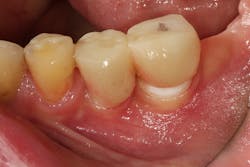

No. 3: Inadequate keratinized tissue around the dental implant crown

There is no consensus in the literature regarding the need for adequate keratinized tissue around a dental implant (usually described as being at least 2 mm in width). Some studies have suggested, however, that a lack of keratinized tissue can lead to pain post-implant placement and/or restoration (figure 3).8

These symptoms are most notably elicited upon palpation by brushing, eating, and percussion. These symptoms can often be treated with the addition of a soft-tissue graft that enhances the keratinization of the tissue around the dental implant.